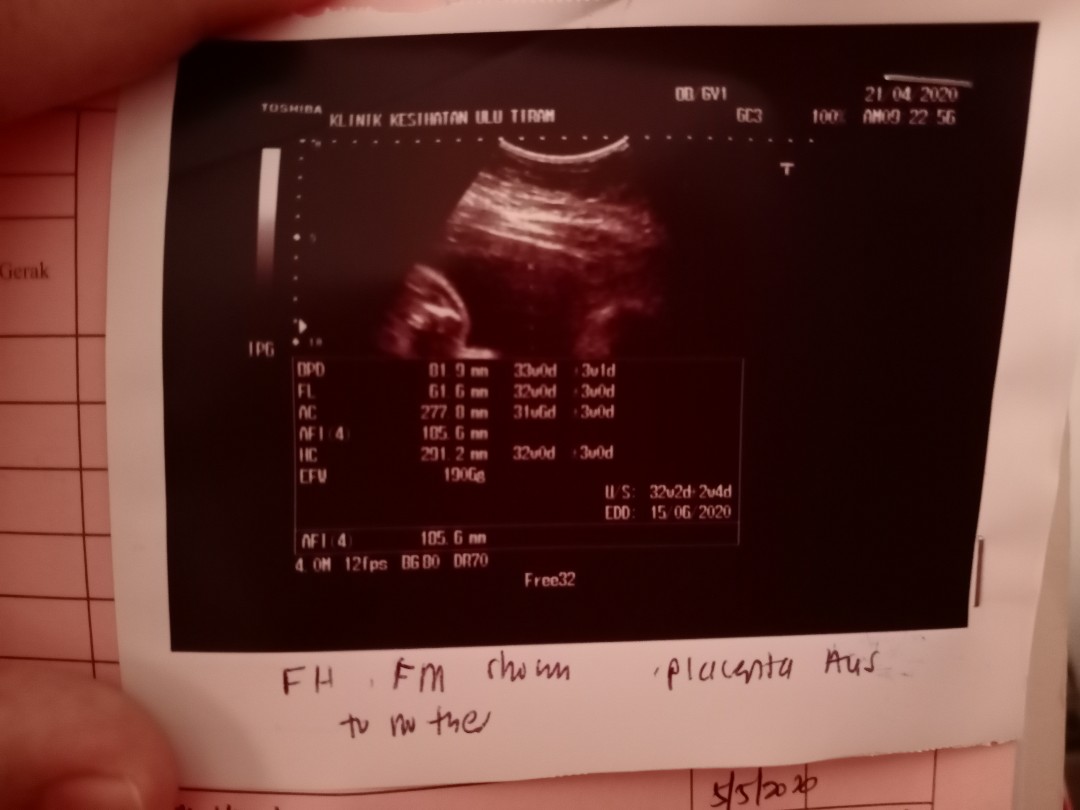

Hai Dr. Can u explain this picture...?

Got a bun in the oven